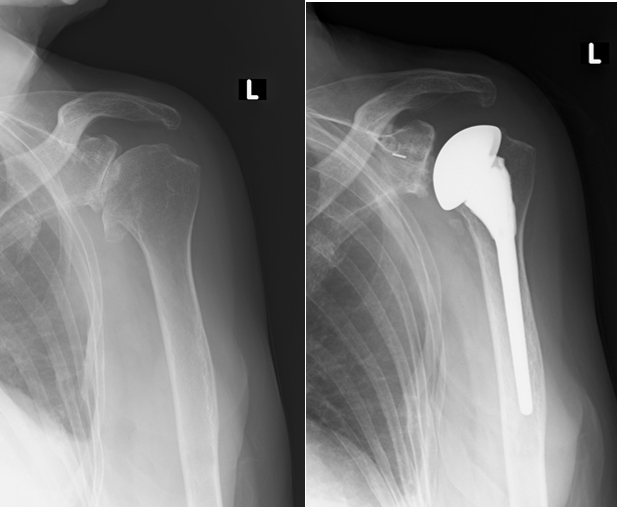

二次性の変形性肩関節症は、腱板断裂などが誘因となり発症します。肩周囲の痛みや可動域制限を伴うため日常生活動作が非常に困難となります。

腱板断裂・変形性肩関節症・骨折の方が対象となり、腕の骨(上腕骨)と器の骨(肩甲骨)の凹凸に合った形のもの(人工肩関節)と、凹凸を逆転させた形のもの(リバース型人工肩関節)があります。両手術ともに大きな差はありません。

人工肩関節

【手術前レントゲン】 【手術後レントゲン】